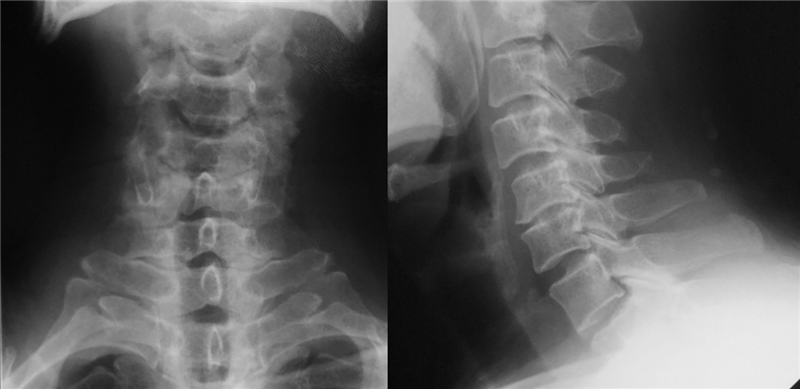

术前X线

MRI:C3-4后方可见脊髓高信号改变

CT:C5-6

软组织窗

骨窗